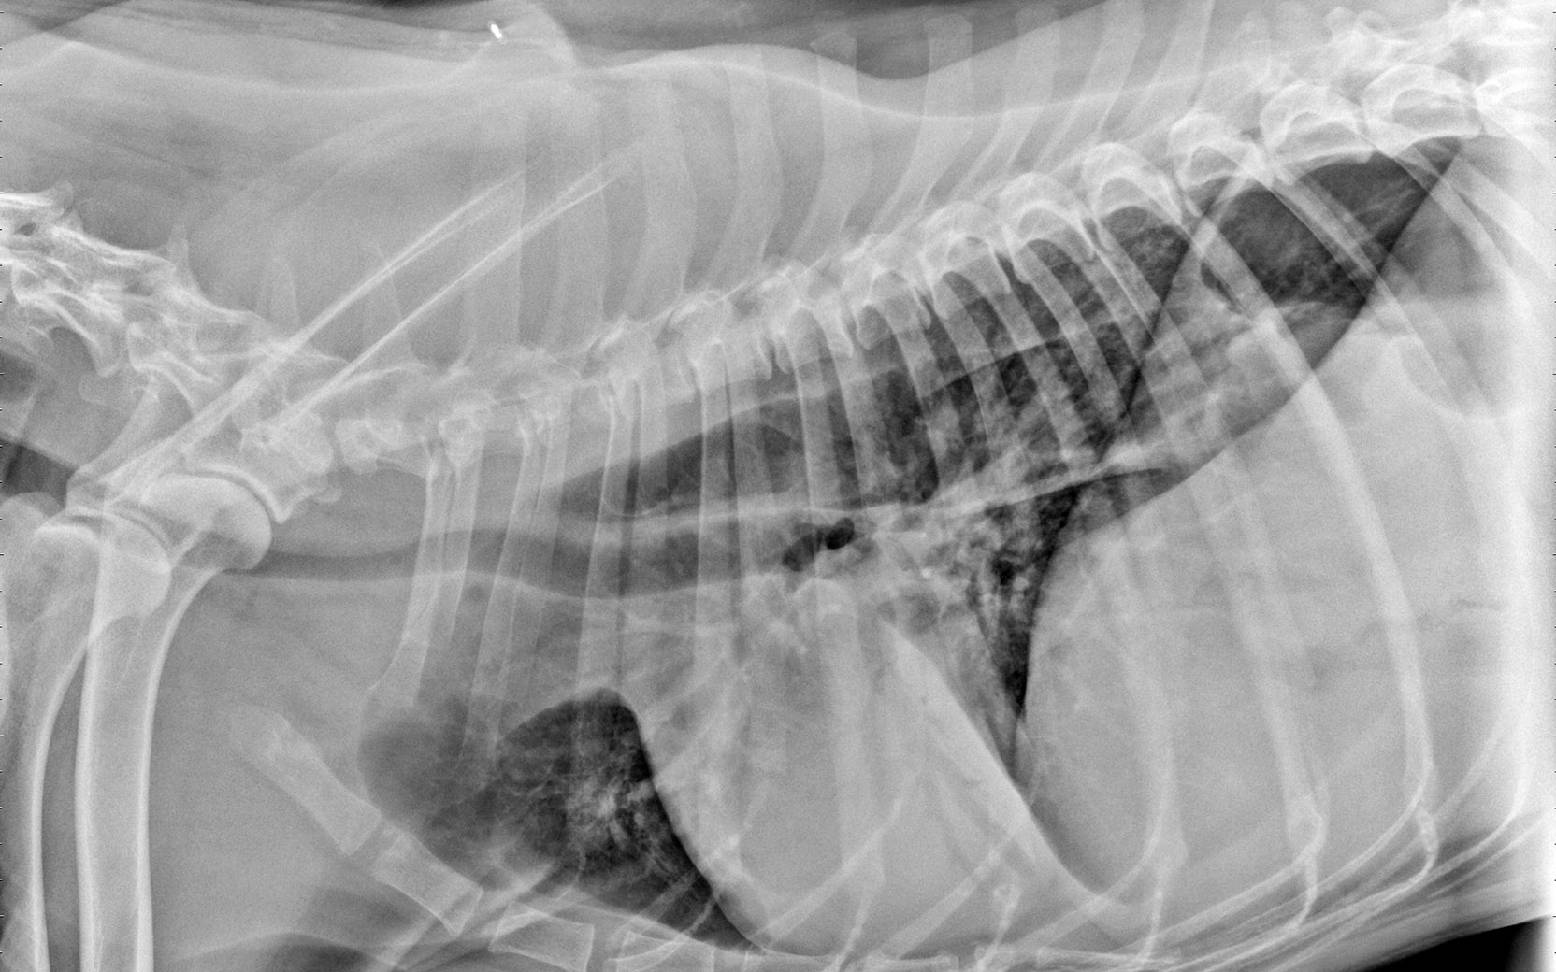

Dein/e Tierärzt:in untersucht deinen Hund klinisch, wozu vor allem auch das Abhören der Lunge und der Bronchien gehört. Er/sie lässt sich von dir einen ausführlichen Vorbericht zum Beginn und Verlauf der Symptome schildern. Meist kann er/sie nun bereits eine Verdachtsdiagnose stellen. Um die Diagnose abzusichern, wird er/sie in den meisten Fällen Röntgenaufnahmen anfertigen. Gelegentlich kommt auch die Ultraschalluntersuchung zum Einsatz. Aussagekräftiger ist jedoch die Bronchoskopie, die endoskopische Untersuchung der Bronchien und von Teilen der Lunge. Hierbei hat dein/e Tierärzt:in die Möglichkeit die Schleimhaut und vorhandenes Sekret direkt zu beurteilen und Schleimproben zur Untersuchung zu entnehmen.